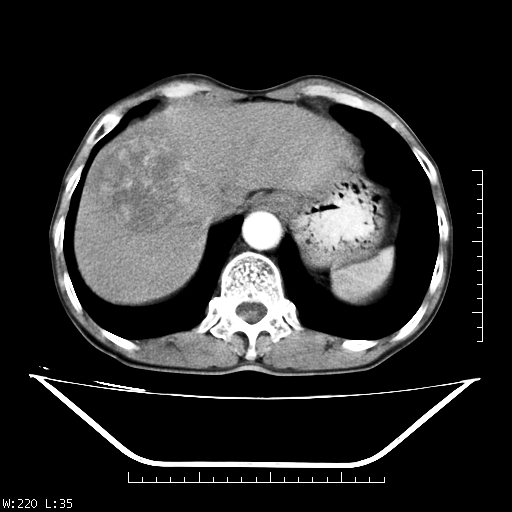

男,70,右上腹痛两月,有乙肝病史,b超提示肝占位,ct如下,请会诊。

补充:该患者afp9.24

肝右叶类圆型密度减低影,密度不均,边界清晰其内可见更低密度影,腹膜后可见小淋巴结肿大,增强扫描动脉期病灶明显强化,静脉期及延时扫描见强化不明显,快进快出表现。

1.肝右叶低密度影考虑为肝癌;

2.肝转移待除外。

平扫呈低密度占位,动脉期斑片状明显强化,病灶边缘清晰,见假包膜;门脉期呈低密度,符合肝癌快进快出强化特征

补充:该患者afp 9.24,似乎与原发性肝癌不符合,另胰头区结构正常吗?请大家继续发表高见。